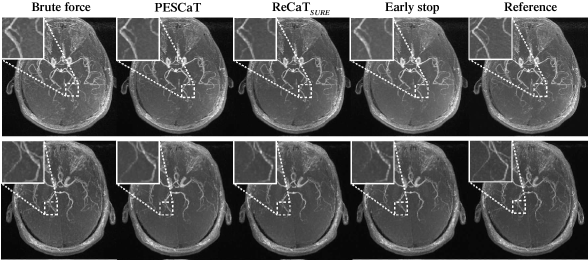

Figure 6: Reconstructions of in vivo ToF angiography acquisitions of the brain at R=4. Maximum-intensity projection (MIP) views of brute-force, PESCaT, ReCaTSURE, ReCaTSURE with early stop, and reference brain volumes are shown in two representative subjects. White boxes display zoomed-in portions of the MIPs. PESCaT yields superior depiction of vasculature compared to both ReCaTSURE and ReCaTSURE with early stop. It also maintains similar image quality to brute-force reconstructions.

Next, PESCaT was demonstrated for in vivo bSSFP, T1-weighted, and ToF imaging of the brain. Representative reconstructions with R=6 for bSSFP and R=4 for T1-weighted and ToF acquisitions are displayed in Figs. 4, 5, and 6. Representative reconstructions of individual phase cycles in the bSSFP dataset, and of cross-sections in the ToF dataset are shown in Supp. Fig. 11. Overall, PESCaT and ReCaTSURE reconstructions perform similar to the brute-force optimized reconstructions. Yet, PESCaT yields slightly lower levels of residual aliasing in comparison to ReCaTSURE, and this difference is particularly noticeable for visualization of small vessels in ToF images (Fig. 6). The improvement in reconstruction quality with PESCaT is more prominent when ReCaTSURE is stopped early to match its reconstruction time to PESCaT.

Quantitative assessments of the in vivo reconstructions are listed in Tables II, III, and IV. For all datasets and R, PESCaT yields the closest performance to the brute-force reconstruction among alternative self-tuning methods. For bSSFP datasets, PESCaT improves PSNR by 1.23±0.29plus-or-minus1.230.291.23\pm 0.29 dB over ReCaTSURE and by 2.55±0.51plus-or-minus2.550.512.55\pm 0.51 dB over ReCaTSURE with early stop (mean±plus-or-minus\pmstd. across three subjects, average of R=2, 4, 6). For T1-weighted datasets, PESCaT improves PSNR by 0.71±0.25plus-or-minus0.710.250.71\pm 0.25 dB over ReCaTSURE and by 1.21±0.43plus-or-minus1.210.431.21\pm 0.43 dB over ReCaTSURE with early stop (mean±plus-or-minus\pmstd. across three subjects, average of R=2, 4). For ToF datasets, PESCaT improves PSNR by 0.72±0.46plus-or-minus0.720.460.72\pm 0.46 dB over ReCaTSURE and by 0.94±0.51plus-or-minus0.940.510.94\pm 0.51 dB over ReCaTSURE with early stop (mean±plus-or-minus\pmstd. across three subjects, average of R=2, 4). Compared to empirically-tuned ReCaTfixed, PESCaT improves PSNR by 0.20±0.37plus-or-minus0.200.370.20\pm 0.37 dB for bSSFP datasets, by 0.45±0.14plus-or-minus0.450.140.45\pm 0.14 dB for T1-weighted datasets, and by 0.91±0.63plus-or-minus0.910.630.91\pm 0.63 dB for ToF datasets (mean±plus-or-minus\pmstd. across three subjects, average of R=2, 4, 6 for bSSFP, average of R=2, 4 for T1-weighted and ToF datasets. Because both methods were allowed to optimize parameters in training subjects, these results suggest that selecting different regularization parameters for each coil/acquisition/subband/level improves reconstruction performance. Compared to PESSPIRiT, PESCaT improves PSNR by 1.16±0.55plus-or-minus1.160.551.16\pm 0.55 dB for bSSFP datasets, by 0.97±0.78plus-or-minus0.970.780.97\pm 0.78 dB for T1-weighted datasets, and by 0.76±0.40plus-or-minus0.760.400.76\pm 0.40 dB for ToF datasets (mean±plus-or-minus\pmstd. across three subjects, average of R=2, 4, 6 for bSSFP, average of R=2, 4 for T1-weighted and ToF datasets). Performance enhancement is even more prominent compared to PESSPIRiT variants that only include sparsity or TV regularization.